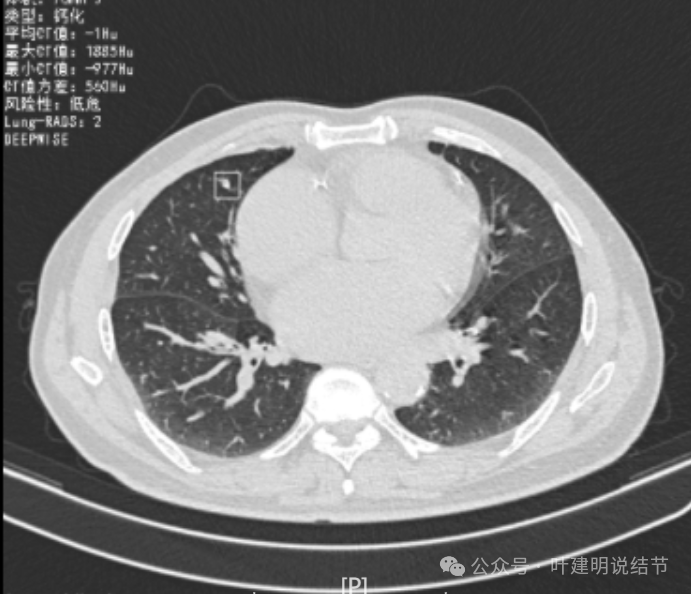

我们先来看2022年3月主要病灶的影像:

右上叶结节实性,密度高,边缘平整,轮廓清楚,像良性些。

右下似见微小结节,实性,与边上小血管截面不太好区分,过小没什么临床意义,能随访。

左下胸膜下实性结节,轮廓稍模糊,密度较高,边缘较光,像淋巴结些,能随访。